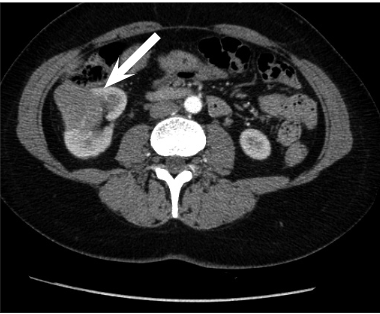

A 52 year old woman arrived at a hospital for a routine health check-up. Abdominal ultrasound revealed a 4.5 cm diameter lesion in the right kidney. Patient was directed to perform a contrast-enhanced computed tomography (CT), which was performed to specify the nature of the formation. CT found 49 mm x 34 mm cyst in the middle-lower portion of right kidney with septum and contrast accumulation (Figure 1), it was classified as Bosniak III and partial nephrectomy was chosen as a main choice of treatment.

Cause of hematuria had to be determined, therefore urgent contrast enhanced computed tomography was performed (Figure 2) – contrast extravazation was found on the lower third of the right kidney (area of surgery), along with subcapsular hemathoma. Right hydroureteronephrosis and fluid in pelvis were observed. Blood clots and a small amount of contrast in the bladder were seen.